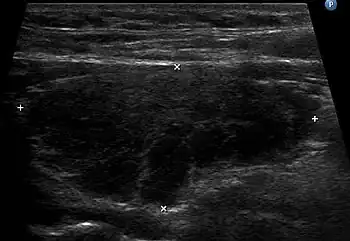

a)Lymphocytic (Hashimoto) thyroiditis-polymorphous lymphoid population b) Lymphocytic (Hashimoto) thyroiditis-lymphohistiocytic aggregates Ultrasound imaging of the thyroid gland (right lobe longitudinal) in a person with Hashimoto thyroiditis.

Ultrasound imaging of the thyroid gland (right lobe longitudinal) in a person with Hashimoto thyroiditis.